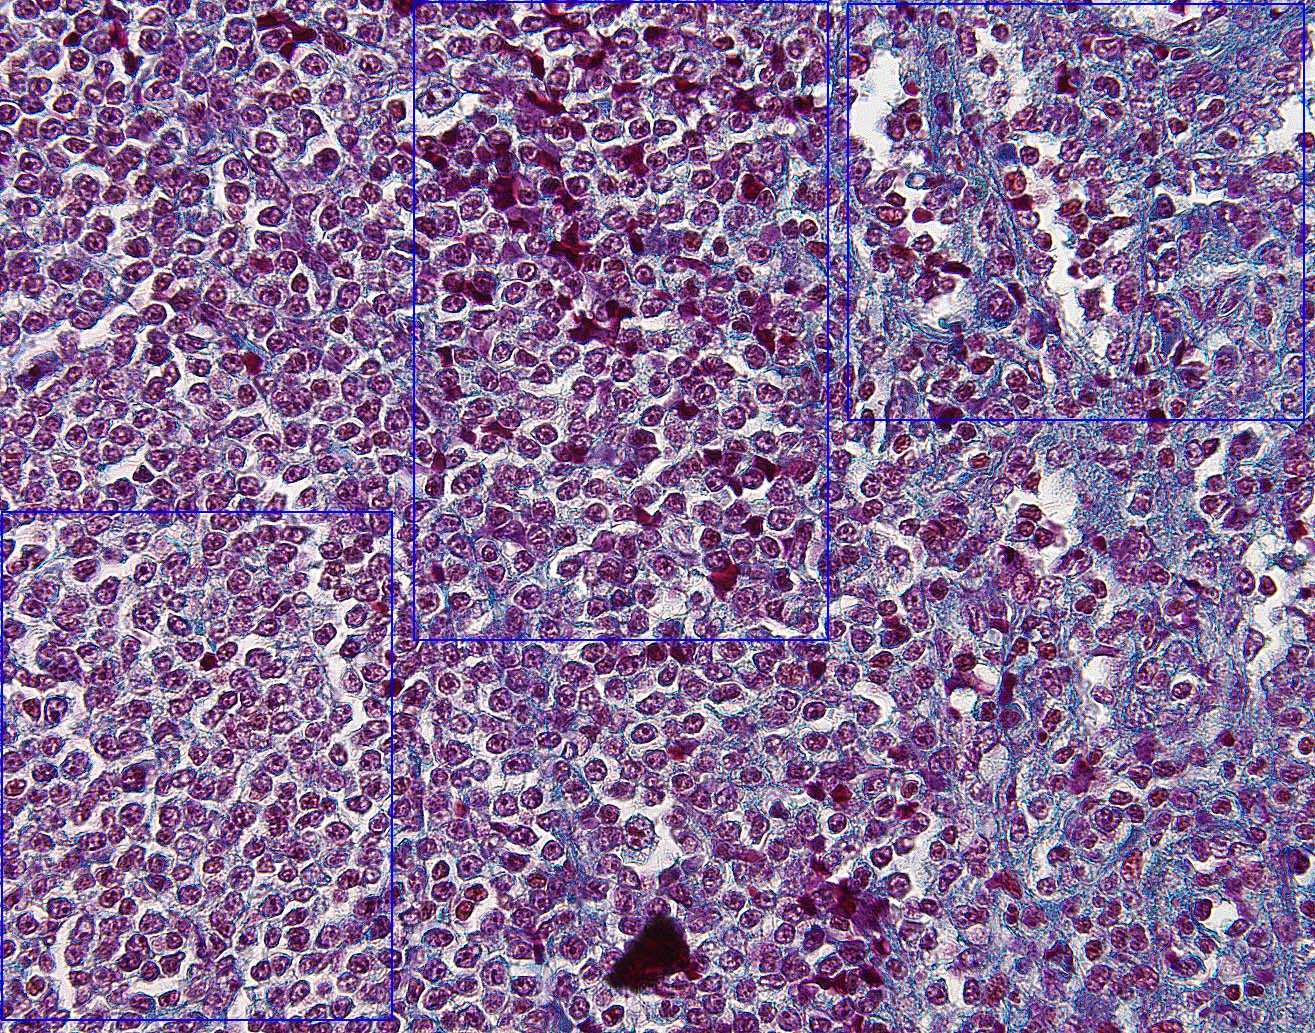

Return To Cartoon of Spleen